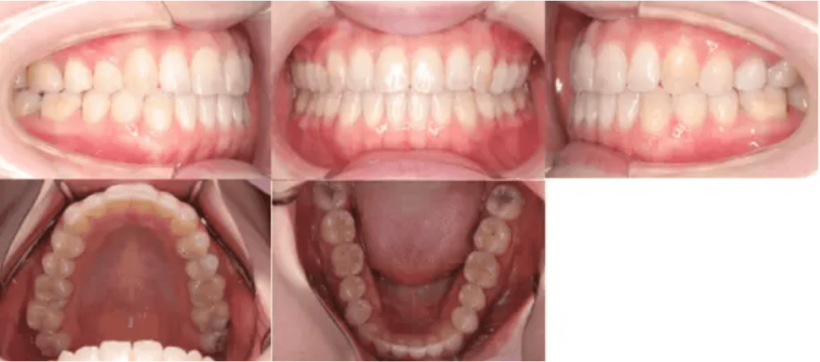

【治療後】

治療例②部分矯正: 23歳

主訴 前歯が出ている

治療内容 前歯に隙間があり、ねじれてしまっていたため、マウスピース矯正で治した。

治療期間 6カ月

費用 40万円

【治療前】